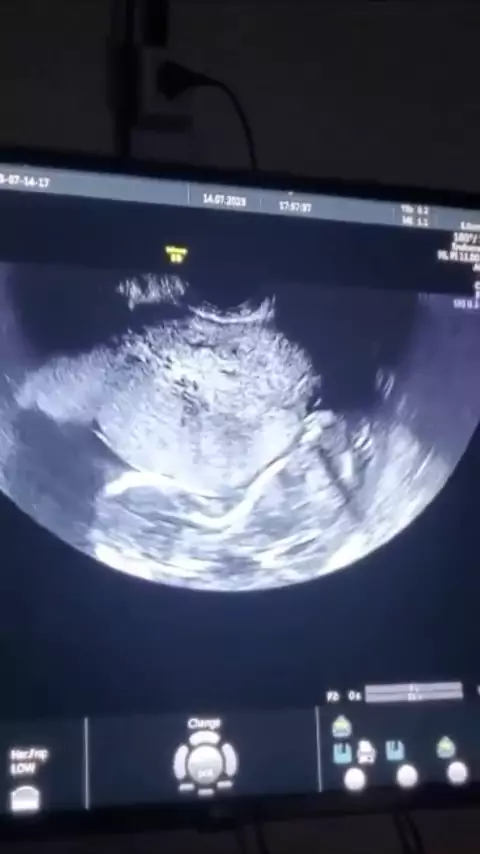

mais um esmeraldino chegando